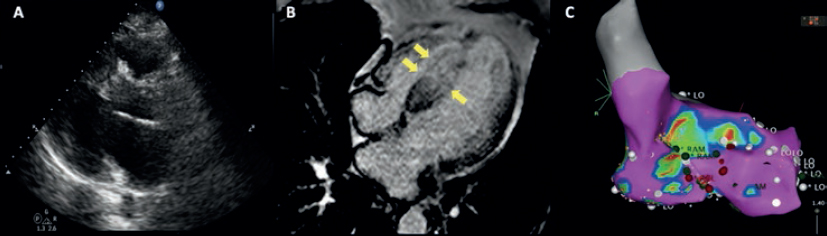

Se presenta el caso de un varón de 51 años sin antecedentes médicos. Un mes antes de su ingreso comenzó con palpitaciones rápidas asociadas a diaforesis, náuseas y vómitos. El electrocardiograma y el Holter mostraron episodios recurrentes de taquicardia ventricular monomórfica (figura 1). En la exploración física se encontró un soplo expulsivo aórtico que aumentaba con la maniobra de Valsalva. La ecocardiografía transtorácica mostró una hipertrofia septal asimétrica obstructiva, con un diámetro septal máximo de 32 mm (figura 2A), un gradiente de 65 mmHg en el tracto de salida del ventrículo izquierdo y un movimiento anterior sistólico de la válvula mitral con insuficiencia moderada. La resonancia magnética cardiaca evidenció una fibrosis miocárdica extensa como factor de riesgo de muerte súbita (figura 2B y vídeo 1 del material adicional). Se inició tratamiento con amiodarona, propranolol y, como prevención secundaria, se implantó un desfibrilador automático. El paciente reingresó a los 4 meses en tormenta eléctrica, con múltiples descargas apropiadas por el dispositivo implantado. Se administró sedación profunda, ventilación mecánica y soporte hemodinámico, y se decidió realizar un bloqueo del ganglio estrellado; sin embargo, la evolución fue desfavorable y el paciente persistió con episodios de taquicardia ventricular, lo cual motivó una cartografía electrofisiológica (sistema CARTO 3, Biosense Webster, Israel). Se intentó, sin éxito, la ablación de un circuito de macrorreentrada septal del ventrículo izquierdo relacionado con la taquicardia ventricular clínica (figura 2C).

Figura 2. A: ecocardiografía transtorácica. Septo interventricular con diámetro de 32 mm. B: resonancia magnética que muestra la contrastación tardía (flechas). C: estudio electrofisiológico e intento de ablación de macrorreentrada septal. LO: etiqueta de voltaje; RAM: etiqueta de electrograma local.